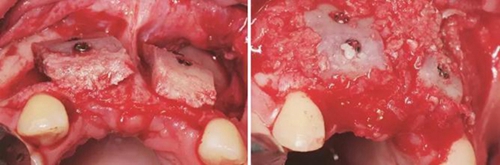

圖5 制取的髂嵴部骨塊 圖6 植骨術(shù)前牙槽嵴頂切開翻瓣

圖7 受植區(qū)固定髂骨骨塊 圖8 自體骨屑與人工骨粉混合后充填植骨間隙

圖9 嚴(yán)密縫合創(chuàng)口 圖10 植骨后拆線

(2)2014年7月:行髂骨取骨,水平向Onlay植骨全麻下患者取平臥位,將取骨側(cè)的髂嵴墊高。標(biāo)記髂前上嵴,在髂嵴下方2cm處做切口,將局部的皮膚緊繃,使其位于髂嵴上方,切口方向同髂嵴,切開髂嵴中線外緣腱膜,剝離骨面附著肌肉至暴露足

夠骨面,使用骨鑿等取骨器械制取骨塊,填塞明膠海綿,分層縫合??趦?nèi)切開植骨區(qū)粘膜,翻瓣,充分暴露待植骨區(qū),用裂鉆在受骨區(qū)骨面預(yù)備若干滋養(yǎng)孔,修整骨塊,以器械夾持骨塊置于手術(shù)受植骨區(qū)并緊貼骨床,使用鈦釘牢固地固定骨塊,植骨塊間的間隙用自體骨屑及少量骨粉(Geistlich Bio-Oss,瑞士)混合后充填,充分減張后嚴(yán)密縫合創(chuàng)口。告醫(yī)囑,囑患者術(shù)后幾天盡量臥床休息,十天后拆線。拍攝CBCT示:牙槽嵴寬度擴(kuò)增明顯:12位點(diǎn)擴(kuò)增至7.4mm-12.4mm,22位點(diǎn)擴(kuò)增至7.4mm-12.2mm。